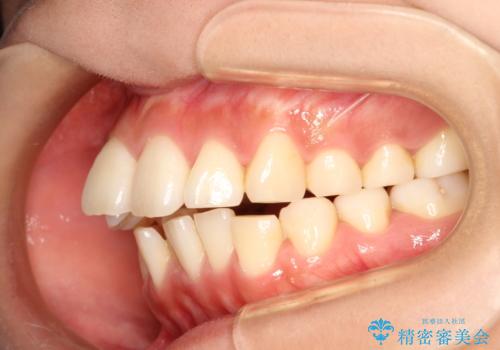

- 上の前歯が出てて、前歯で咬めないとのことで来院されました。

上顎の歯を1本抜歯して、前歯のガタガタと、前方に出ているのを改善する計画としました。